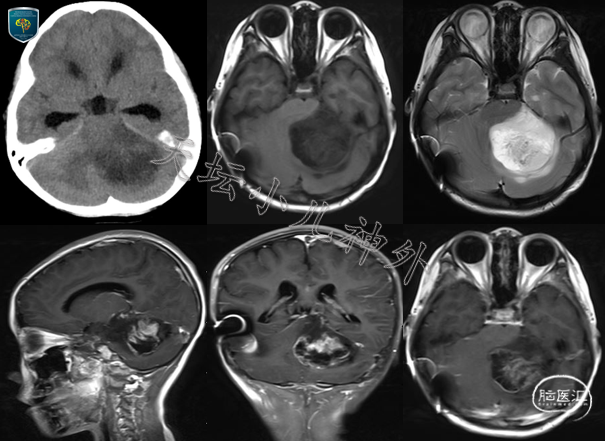

2021年2月接诊一例来自吉林的8岁女性患儿(身高:122cm,体重:20.0kg)。主诉:行走不稳20天,头痛呕吐10天,进行性加重。患儿20天前无明显诱因走路不稳,10天前出现头痛呕吐,逐渐加重并出现嗜睡,于当地医院检查显示:颅内占位伴梗阻性脑积水,遂来我院就诊。门诊查体示:神清、精神弱,双瞳等大等圆,左:右=2.5:2.5mm,光反应敏感,余查体欠配合。头颅CT/MRI示:左侧小脑半球占位,胶质瘤可能性大;伴梗阻性脑积水(图1)。

图1 头颅CT:左侧小脑半球团块状混杂密度影伴瘤周水肿,梗阻性脑积水;头颅MRI:左侧小脑半球、蚓部不规则团块影,长T1长T2,大小约63x36x52mm,不均匀强化,胶质瘤可能性大,梗阻性脑积水伴室旁水肿。